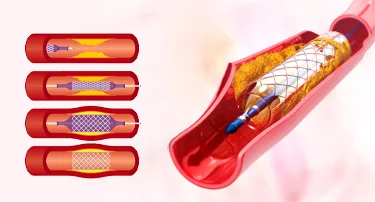

Carotid Artery Stenting vs Endarterectomy: Which Is Better for You

Stroke is a serious condition that happens when a blood clot or broken vessel prevents blood from reaching the brain. Due to this, one can experience paralysis, muscle weakness, slurred speech, and memory challenges, or even seizures.

Carotid Stenting: A Life-Saving Procedure to Prevent Stroke

You might face many instances in life where planning ahead could make all the difference. For example, if you want to crack a competitive exam, you analyze the past papers, concentrate most on the important topics, and then study hard to get the best outcome.